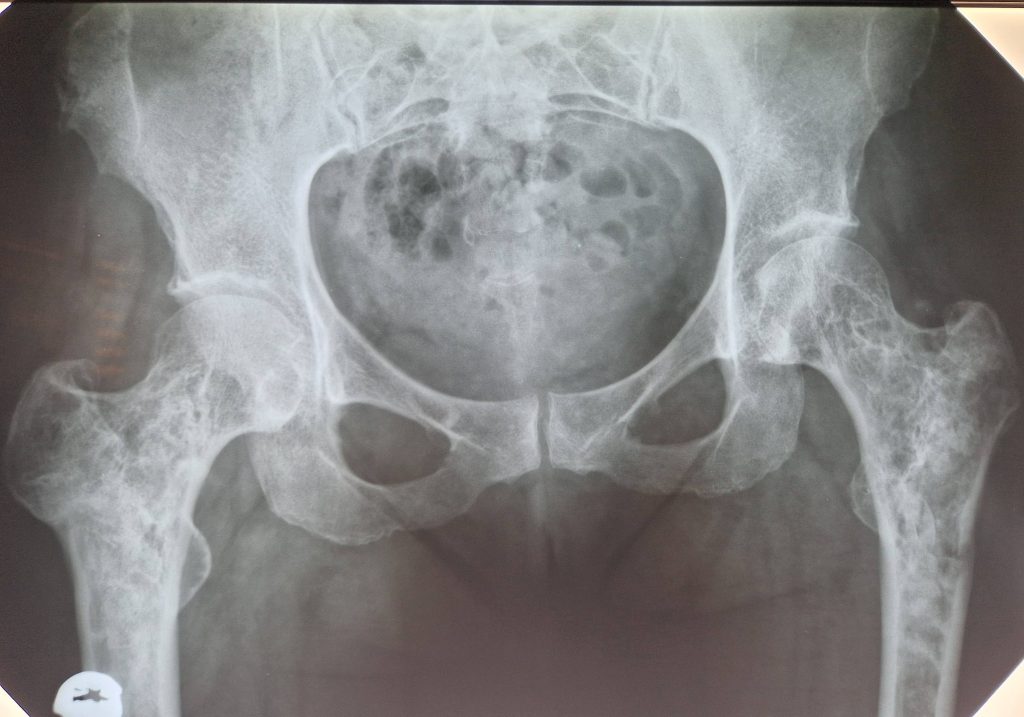

Рентгенограма аневризмальної кісти проксимального відділу обох стегнових кісток. З метою підтвердження діагнозу проведено біопсію вогнищ ураження. Наступним етапом виконано операцію видалення вогнища ураження з заповненням порожнин аллотрансплантатом, спочатку з правої, а через 6 місяців з лівої стегнової кісток. Рентгенконтроль через 6 місяців.